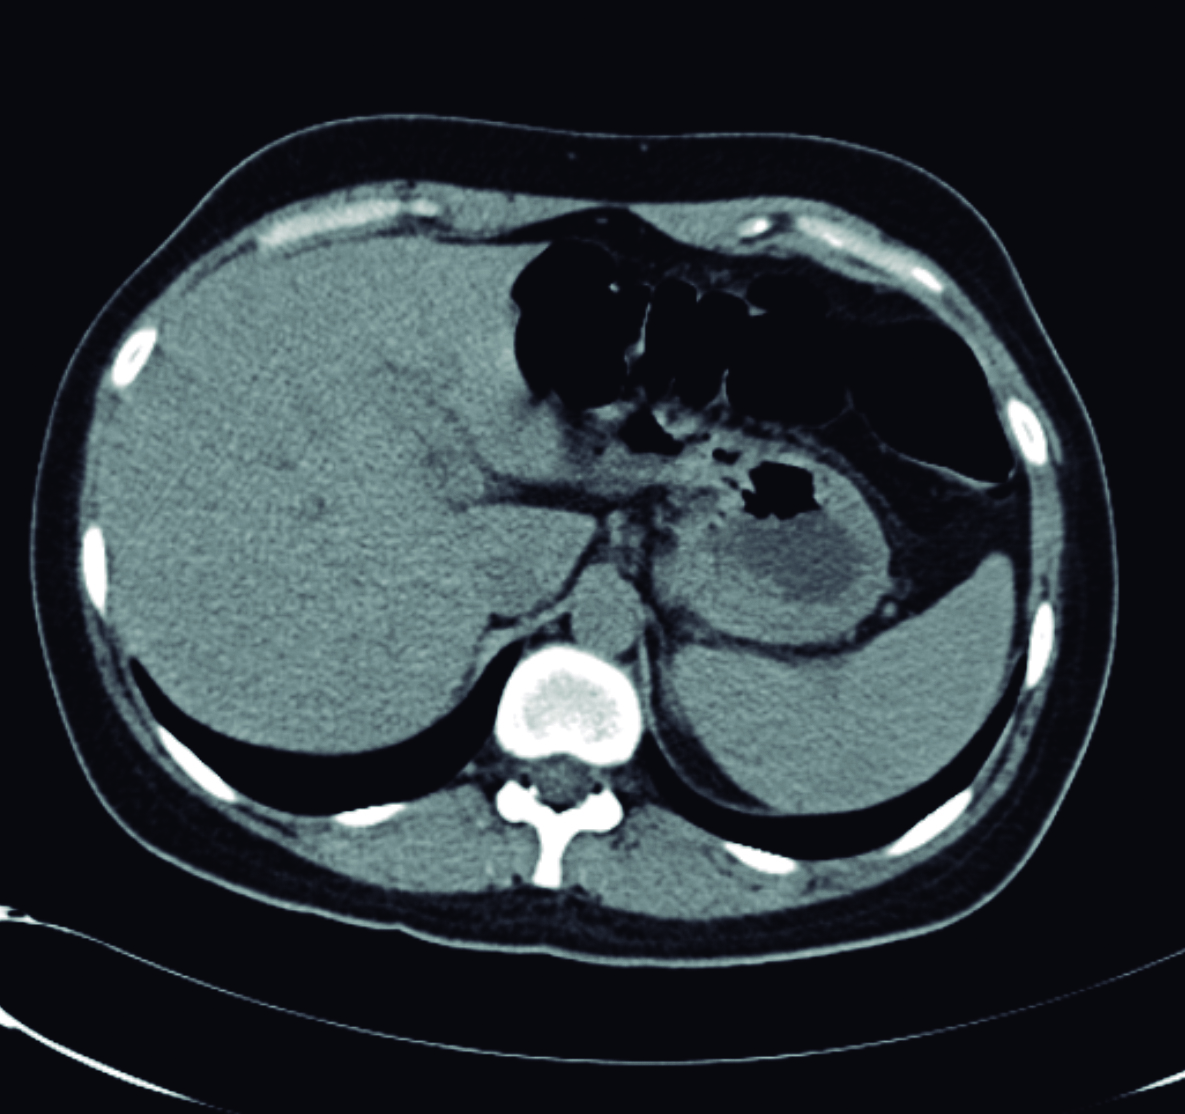

Una semana después se realiza ecoendoscopía digestiva alta, la cual informa colédoco de 9 mm de diámetro, en cuyo interior se observan dos líneas hiperecoicas alargadas, paralelas de unos 3 mm de diámetro total, compatible con Ascaris (Fig. 3).

Figura 3. Ecoendosopía

a y b) Líneas hiperecoicas alargadas, paralelas de 3 mm de diámetro compatible con Ascaris (mano).